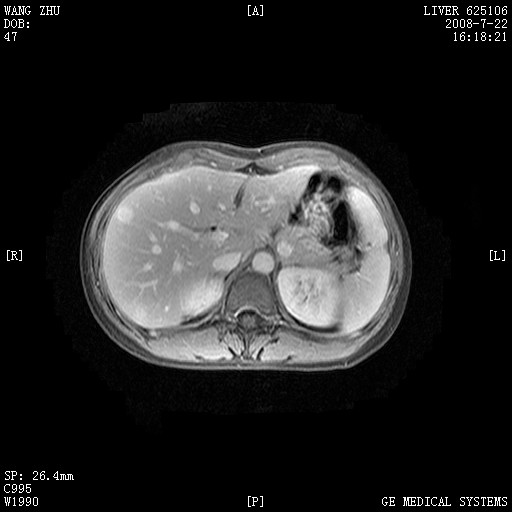

图像有点乱,病灶边缘清楚,可见纤维囊壁,灶旁可见异常灌注,增强显著增强,病灶有早期完全充填,无快退征像,考虑炎性病灶,肝结核可能性大,不知有何病史

肝前外缘见一类圆形囊性病灶,边缘强化,灶周肝为炎性渗出改变,其肝周可见少量腹水,符合炎性病变,病史较长---考虑腹膜结核。肝为外压性改变,脾为动脉期改变。